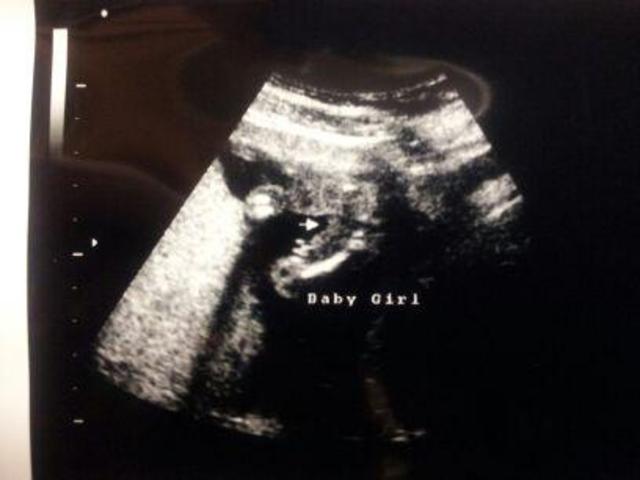

Image

Months 1-3. (1-13 weeks)

2nd Trimester

[Image ](data:image/jpeg;base64,/9j/4AAQSkZJRgABAQAAAQABAAD/2wCEAAkGBhISERQUEhQWFRUWFxUZFhcYGBQYGBgUFhgYFBgXFBQXGyYeFxojGhQWHy8gIycpLSwsFR4xNTAqNSYrLCkBCQoKDgwOGg8PGikkHyQqLCwtLCwpLCwsLCwsLCwuKSwsLCwsLCksLCwsLCwsLCwsLCwsLCwsLCwsLCwsLCksLP/AABEIALUBFgMBIgACEQEDEQH/xAAbAAACAwEBAQAAAAAAAAAAAAAABQMEBgIBB//EAEQQAAIBAgQDBQUEBwcDBQEAAAECEQADBBIhMQVBUQYTYXGBIjJSkaFCYnKxFSMzgsHR8BQkU5KisuFzs/EWQ2PC0jT/xAAZAQADAQEBAAAAAAAAAAAAAAAAAwQCBQH/xAAqEQACAgICAgEEAQQDAAAAAAAAAQIRAyESMQRBE1FhgfCRInGh4TJCUv/aAAwDAQACEQMRAD8A+4GkP6aILKd0YqfMbfMEH1p/WO7TILeLU/4yH/PagT6qwH7grUTcEm6Yz/TlH6cpBRW+KHcEP/05R+nKQUUcUHBGhs8al0X4mA+YP8qeVieGf/0WPxn/ALdyK21YkqFZFTCqfE+KJYVWfNDXLVsZRPtXXW0k9BmdRPjVylfaLhj37SohUEXsNc9okCLN+3fI0B1ItwPOsiyduL287pP7Jc11tAtsEZgHY6A5dY5CCYBE84Ljdq7cdEOqZNTEMHTvAU11GU1n8Z2IZ7t5gyjvLl65m1LHvcL/AGY2nEQUDAPv9hREia5wfY+6t21dPdAo+GYwWJC2sO9h1UlBuXBG0jegDX94OorzvlmJExMSJjaYrO8c7Jm9de7adbbMlsyVn+8Yd8+HuHwGZ1YbkZRpFVMb2Nus94KbYRlY2bhN3vLTmx3BXu1hGQwWJkH2mETDAA0b8WQXbdrUm4lx1YRli0UVpM7zcX61drF3uyOIJtXEFi2698zoGuvbuPcawcr51lkYWDMAQSpAJUzsk2E6Hw29KAOqKKKAFGL7TWrV027oe2MlxxcZf1bCyoe4A0zKqZ1ABgxMGu7PaOy0gkq4OXu2gOW7rvwAJgzb136jcUv4twK9iXvLcFoW3tXbKOGc3ES6kMRbyBcxYLJzbKAOc17nZO614XybZuG7mYS0BBhWwwCNlmc7F9toE6SQDRcO4kl+0l1PddEcTEgOocBgDoYYaVY7wden12rO9l+zDYYMr92VaxhbZCzDPZtm27MCokNI8YGtUrHYV1UqLwANi5YkLqFQsMGw+9aS48nmcu0CgDW/2hYnMIJiZETtHnPKq/D+KJeDlZGS5ctkNAOa22ViNdRNZd+yF5gpZMN7XeLftB8T3bZ1tL3qt72cdwBlgCGjNIkseB9n71jEXbjMj27r3mjXNbzOXXuzl2YN7Sk7oCDqRQBo6KKKACl3GuNLhrZuOlxkUMzlFzZLaiWdpI0A1gSTrAMGmNKe0GEvXUCW1tMjT3q3HdMy6exKo0g7N1GnPQAlxHHrKXUtM0M1u5dn7K27eXMXY6L74+R6V1guN2rruiEymTUxDB0FwFNZIg0l4n2QuXb3ed8YNnFIyMFK576W0GWEzZB3exM6L4zXwfY+6t23dPdApcwzeyWJC2sO9h1U5BuXkbSN6ANf3g6153wmJE7xImNpis7xzsm166920622ZLZErP8AecO+fD3D1ADOrDmMo5VTxvYy6zXgpthGVjauE3e8tO1gYcrkUhWQxmJkGGYRMMADSNxVBdS1qS6XHVhGXLaa2rSZ3m6v1q7WLvdkcQTbuILFt175nQNde273Hw7ZXzrLIwsGYAglSAcpnZJsJ08v4UAdUUUUAFZbtfbm7h/AXT9bX8zWprL9q7n66yv3Lp/1WhXsezeP/kKa9ooppSFFFFAHnfZCr/A6Mfwhhm/05q3ltwQCCCCJBGoIOxBrCCtX2cI/stmPgE+Y0P1msSFZV7GVFFcs4AJOgG58KwIOqKSY/tOigdyhvFjCkEKhO+lw+8AJJKhojWKqXEuXNbrT9xZW2PDLu3m0+Q2rEp0Ox4nM0oavayI4da5W0B8FAPzGtT2MVcte6xdeaOSf8jnVT4EkeW9Y+X6obLxmumaeiocLiVuIHXUMAR/IjkRtFTU4kCiiigAoqlxDii2oEFnPuosSfEk6KviaUX8Tdf32yj4EJA9X94/QeFYlNIdjwymaF7yjcgeZAroGsqMOnwj1APzJ3rlLJTW0xtnfT3D+K37p9IPjWPl+w5+L9zW0Ut4VxfvPYcBbgEkDUMPiQnl1G4nyJZU1NNWiWUXF0wooor0yFFFFABRSbEcdLErYAYAwbjTkBGhCga3D5QPGqN3Cm5+1uPc8JKJ6IkfWaW8iXQ+OFvvRpHvKNyB5kCugayn6Hsf4Seqg/nQvDLa/s81s9bbMv0Bg+orHyv6DH4y+v+P9msorOWeL3rP7X9db+NQBcUfeQaOPFYPgafYfEK6hkIZWEgjUEeFMjNSETxuHZLRRRWxYVje01wtiwBsloZj4s5IXwJyg+XnWsxmJW3bZ291FLHyAmsMpYks/vuSz/iPLyAhR4LWoobiW7Pa9orymDz2iio7t9VjMYnYakk9FUasfACgCStHwDEpbwoLsEUNdEsQB+0fmazdrB3rmwFperiX9LQOn7xn7taTgXBLaW0cgu+pDOcxGYlvYGyTP2QKxJisjTRP+kblz9hbMf4lwFF81T33+Sg8jXq8FDa32N47wwAtg/dtD2fVsx8aZV4awIM6v62+9w7Am2ngiNDerOpPkq9KLz66V5YBXMvNXuA+rFh81ZT61yRrU1nUxJHq1zeGldMYBIExyrlLwYHw0I6HQ/kQaVIZey/2bb2Lg6XDHkwV/9xanFIOzl79ZdXwRv9yn8hT+qsbuKObnVZGFQ4zEi2jOdlBMDc9APEnT1qalvHSciDkbiT5A5vzUVtukKirYttKzGW99tWPKeg+6Nh/yajusBtXeaJquR1qOcqOxjieKalRqjgaTHlzPpUoFL5DZUQYhToyGHUyp+94+B1B8Ca1GBxQu21cbMAfKeR8QdPSsxf5+VN+y7TY8nugeWcn+NUYXsi8uC4qQ3oooqk5wUi4tjDcZrKEhVjvWGhJInulPKQQWPIEAamQ1x+J7u0775FZo6wCYpFhbJVQDq2pY9XY5mPqxNYm/Q7FG3Z3btgAAAADQAaADkAK6LVMwAWqFy5U05UdDGuRK1yvA1V1ephS4yGuNEhaveEXu6v8Ad7JdBZRyF1dXAH3lObzVq5I0qpj7mXu3+C9ab0LZD/pc01OtiJw5KjX0V4KKrOWZ3tZi/wBnZH2pd/wIRA9XK+imktWuNvOKuz9lbajygufq9VabHoqgqQVZS3lIAgvrMxCfPSRuTy864wuhLc1UkeegB9M0+lTvaAVUAzFlzPJIEESASCNANd4oPWytYuvdu5EvMFylmjVyNIlWlbasCYkMT0WmuH4ZataosFhqxJZzy1dpJEjbalWDxww8i6QyMZ71R7S9BeMD2RsGGg5ge8XpefKNPKsK/ZiXeiJ1J0G5gDzOn/PpT9FgADYUr4fZl55KP9TaflPzpqTXjEyZ7XhrlLgNUuN8QNq3KxmZgqztJO5A1Ok7VlulZ4k26RmuOcSuJee4oBAJQpGjC3JzFp0b3tI2jpV7DvmElSv3TEj1Gh9KXcSW4xLlEYOjB2BKkEKdY10I9nQjWNtal4dYvAPAF05lJ9qGCsNCM0BxodZBkHeKk25M6iSjBehgdKq2Egu0+8R8lECTzPWquJ4oQ2QIwIZVacsKzaASGOY6iQNudXEb2u7USwjOfspOonqT0HrFeKmxi0rPeHtkxVs8nD2z5kB1/wBhH71aqslxJYXMnvIQ48WQho9Yj1rVWboZQw2IBHkRIqjF1RD5StqR3VLi+GL2iF94EMviykMB6xHrV2l2P45ZtMFdtSdYBbLOxePdH/naaZKq2TRTvQqS6r6r/wAjzHI0XFqpg74ZyUaZzG4I0zF3dcrdIcjSQYHreNRTVnWi6FWOw2hYTpBEMRrsZGxnQa7RpV620qp5kCjEJpEwOfiOk8q4R525UtQ2O7Rzingehp72eslcOkiC0v8A52LD6EVm+MWSbbeRB8jofpNbVRVWJbIvLl/TFI9oooqg5wr7TGMLc/dnyzrP0mqnM024lhe9tXLfxqy+pEA/OkeEvZkVjoSBI6Nsw9CCPSlT7KcP7+/gnv7VQI1q+2oqA26jyl+N0iELUqCvFWuP7eswNd+a6kbhZPtR4VmOjbdkzH6Uu4wf1TRvKAeedY+tXjdBAI1BqFbYe9Zt9XDn8NuW/wBwUU486VmsFFe0VacUxPFD/eb/AONf+1bqCrfHLeXFXPvrbcfI2z/sHzqpTV0Vx6R1buFTI8RrqCDoQR0qa/is0wILQDrpAj2VHIaDrsKr0V6e0FRWLj2dLYzW+dvSVO+azOg/AdDyjnLRQDVmq7P4pLlkOhBzE5t9GGhUg6giAIOulMLsxpWL4LbK337tsj3FzCZKO1uFZbijeVKww1GU7iQdXguIh5RgUuKPaQ7gbZlOzoeTDyMGQFNEslTKGPxKbPCnlm0+R50iu3QxAS7MGcoZuhHJgR5gjxptirpTEszGbeYLcDagKUUq0HQBWmY+IzTfG2LT24uBckbmAB4huXmKRXKx98K72ZtMWGOW5Cty10YdQTrO0g6+YINR27T23yFyghgrLu1o693J2YGIPwyRrNRvZDoyBg8OQpOqkA6ZojUqRqI3JB2qzZTvENq6ZdI9rYkD3XHQ6ehBpTTWyqE7/pZXTILpgBbdlZ/eadSeZChj+9U+GYrZkiGcl2B3ljIB8hA/dqpwzh7Kzo05Q4dmJJz+woQSdZlSxGw0jQ1xxjGEnInvNoI3A5keQ/hWLpFMYc5UXVc5Mx/rlTzs0xOGtTyBX0Vio+gFIRZFuyqjkB/RnetB2ctFcNanmM3+clx/up+Psl8uuP5GLHSszw68CokyXlm/ETLfImPCAOVaYmsdxLH2M7XAGtupzggsVuqCVbMsQCVBhog+z7XKtZNbJcG21R3a4e7NdW02RhlYLsGS4TmCn7Bzq5kc3MjUVFc4ibcq4K3B9ljLHoRHvg9R+dXWukZL1v2im4H27TRIHjoGHio60/TGWzbFwMMmXNm5ZYmZ5ClximPllcHdWjCY175ZRcU2gy5hsWIkLGUaqxJGm+vKn3DsHkQZlA6ayaia4Lt7+0MIULltA75ZkuwOxbkOQ8TA9u4uTJOvLypbqLK+c8kUqolxiqwII0IIPkdKacFxZe3De+nst4xs3qIPnPSlQMiuOGYnJiVHK4GQ+ajOv0Dj1reOexGbHyg/saio799UUsxCqNyTAHmTUlZ/tLdzNbtgE5f1jRlkZdE9/SCc3+WqJS4qzn44c5UW27TYYCTcA0nUMPZ+IyNvGlmIuL3rCy6srKbmhDANIDjQ7GQ3mWpLduot+2QqQGMkgLBAOZbijQkbqfHxpldxKW7r3ChytaULkUnUMxYaDeCN6m+S+y9YFB2rJcJxW26++uYEhkBzMGBgwBuOYPjVveluBuW7rd5akaCTBAYa+yw5kfMTTIUtq0NdJkYFU7wzPcGk5VGvw6kR0E/nVq48Uuxd3McpPsmJEGT92Z2PPwpVDsab2ifAv+rB6l2HkzEj6EfOpOHt/fLJ6peH0Vv4GrFvCyBOg6VQxl0Wblm4dAlwSeWRxkb6NP7tPSrbFyakpJd7NnRXgoq04wn7R8LNxVdBNy3MD4kPvJ56AjxUdazKOCJG39cuXlW/NYjtPYe1igyLKXEzMvMurZWZPvQySOfnW4v0Oxy9ENFAFEVscFFEURQB7avZLlp/guIT+Fj3bf6XPyrUceFsW875syn9WyQHVzp7JOg8QZBAMg7VkcWhNt/wt84MVrOL4Nr1lMvvCGjzUqY5T7X/AIpWS6tC5JOSsUJxIsS13LJQaqYDhSwJj7JGYSNdwQYIqC3iUBAS1rrkEHYb5WbRQJGo0E1YNpXXQAyIIKggxoQyMNCNuRG1V72JFtYLs7gakksYXlzMD16kk61FJrtluOFaSO+4UklmbvGGrIzKB0CqDy6mT+VKrVm5h7oESCSVYCJ9n2g8aahdT1APUC9h8Leyd8wAtnLA5kNoHEbDUb7gzpGt4AXUg7+G4I2I8RWWhjcdpO0UcXxtcnsmZ5fazbRl61xwnhp/aXPePL4QOQP8ec1NhcEpYllAuLv0IOzL4H6EEcqvsYFHG9sc5qMeMCjxe97Bj4THy0rXYOzktovwqo+QA/hWNNrvbiW/iYA/hHtN/pB+dbZmAEnSn4vbOd5b1GJR46pOHuRPu8ugIJ+gNZTvAcSMhAgMT7p5dFPMHnqI8YrZDiFo6d4n+YfzqA8Aw5M90nyAHqo0Nezg5dCcWVY7tGd4Pegtb+D3fG00lY8Acy/uip/7EoD5mJtlwwtfZNzcsRzEwcu0gnemHEuAIP1tlAtxZ0XQOv2kKjSTEg9QKyfEOLO7BEEyCeYESBr4ydt+sUmScEW4uOZ/QY4viaiSxpai37rSfYU7ADX1J2q3w7gxPt3Pe/LyHLz3p0lqBET4ilqL7Za80MeobOLYyqBuQN+dLMTiMl6y3S9a+THKfo1ML5yjWlhs57loH/Ft/wC4f80J70KSXGTf0ZvBSTtNwwOguQSbc5gpILWz7wBBBke8Pwxzp2K8ir5JSVM4kJOLtHz7EcJKywzXVcaMACwGvsxEFWB96NI6bXuDYhsuRwQyaEGJjdSY01WPWaa8V4HlGexmBBlrSn2XH2sq7K3MREkeNIL1zK6XVMq0Kx9fZJ9SR61Dkhx2dbFlWVUyXGWrlgNkYi0xZjlUFlnU5Z0ImT1151cw2PV7YbOG+9EfMcqu2XBA6UhxvZpnu+yFt2hJAKqzFjuVAiF6BiYkmBWFdaC03UiHG8ZkkWyNN3PugefWpeH4N2IZZk/+441j/wCK308T9aYYTgVu3BPtEbFoMfhWMq+gqzdxYG1Cio7kxzytrjBEY4Uuhclz95mJ+QgD0FR4jAKVdWkowgqSTH4Sdq5fFE1OoOXWtN2rSM8ZLtjLs7jmZDbuGXtQCfiQj2HPiQCD4qaKQ2uIGzeDjmjKfRlK/m3zoqnHlXHZzs3jyU3xWja1S4jw8XCh+En5MIP8Ku0U8kWhV+hRR+hRTWivbZrkxV+hRR+hRTWii2HJiluCAgjqDTRFgAdABXVFeWeNtiziHBRcJZDkfmYkN+Ic/Peu+E8JFlSNCzGWaIJPIdYA0AphRWeCuzfyS48L0KcRww28xsqGRp7yxICtmnMbROiMZ290+BOas/hMSMzBSfZMEEQ3hnU6ho3nnNbalvE+CJdOYexciM4EyPhcfaHTpy5zjJBva7GYMqg6fTFDAF1cNlieXvKR7p8JAPpVfiGNAGn9T4c/+am/9PYkaA2465m/LLTXhfZ9bRzsc9zqdl/AOXnvSlGT9UWzy4oK07K/Z3hDJN24IYiFXmqnU5vvEgacgAOtMccwjX0mrlc5BM86oUaVHOlNzlyZmMbfLFQymCRlLJ7ObkQ0af1vXC9pO4Q24JOY92TmK5IBOUjViGOUINfaUbajRcSwXe2ys5ToVO8MpkEjmPDxrInDMtxi4QtakIVLZS7gEnXaFgfvGkzuGx+JLJr/AAO7fFMUBL2rcfCHIaPHQrPhMeNL+K8TtXblhrZGcd6GRtGXRWhxyMoNeYkiRVPh/Es7HNIYGGB5H+VTcU4fJF1BLqBK/wCIoM5T94HVTyOmxNL+RsqfjqD+4wtOSmYCNSCOhGn9eddouk+0PKqXDsWGhlMqwhvlKmOvL18Ks3HjlPkYryb1YKDTopYkmSTp5/wFc8KScRbH3ix/dVj+cVxiDzgD6mrfZa1mvO/JEj1c/wAk+tLxK5FOZ8cUn9jV0TVTF6iC0DwkfUUlxV64hHdXmUSMyND+z1QsCQfDY+FXt16OHGKfs01ZntBw4IS8fqn/AGg+Fjpn8jsehg9atHiF5RIZLv3SChI8GEifSrVri1t7Ts/shAe8VoMCJ/eBG3XbfSsyqSpjIXB2tmY4djCjG2+6xB6qdj56EHxFXbvEelUsPwNXUuQ6FiSgzHMlvZbZmeWsdT4VWucAndnI8Xb+FSSg0daDhN7LeI4iBqzAeZAqhc4pPuKzeMZV+bfwBq1heBIDpv8AM/M60wt4EDlWPjGucIdFPhuFvZg1wKUjZTEeciT8xV7GXNKkzQPClPEMZI01nb+Z6DxocqVGUnklZZ4VgRiLrA6Ii6n77kFR6KpP7wop92Yw2TDW595xnY9Wf2tfQgeQFFWQxrjs5WbPJzfF6GtFFFOJQooooAKKKKACiiigAooooAKKKKACiiigCpxTHCzae4dcqkx1OwHqSBSXgHFmBPfuSHIysfdD81+6DpHLTkd3+Lwq3EKMJDb/AJ/mKzvdi2e6uiCc0GPZcc4G3PVeU7RScjaafopwqMouL7HfE+Id0mgl20RereP3QNSegrJ8Sxa24WZM69WdjJ0G5JJ0HWrF4JZVmXUhT8RyrvlQEnKNBoPCvF4atnD57hU4i6bUSRK5nQhEHhzI3g8opU28n9izDGOBcntvr9+iEDM63O8f2cxClfhGyknrJjyPhWowj5ljpUGHwK3MWFYArlcwftDLlj/XPpUNpjYutaYzlgSeanVW8ZG/iDWFG42UZJqUuK7pM8e33Fwv/wC0x/WfcY/bj4STr0OvM1fdOYMg8/5VJdAO+xEH1rnF3wqwumkkbCvL0ZttoWY+4PkKe9k8ORhg50Nwl/Q6L/pAPrWas4U4i6tpZg6ueiDc+Z2HifA1vrdsKAAIAAAHQDQCm4IexPnTUYrGv7spXsE7HRlX90tPzIilHFLdtCA2IPejUKLYb/MiDMFPia0rsACToBufCslwviTXlZ7VrNnZ2Zico1JCqDBLEIFHQRE02ddEWK3v1+Du3jGZrYUW2BYhsrNIGUmWRlDKBA36jeahvgNigsyoTMw5Flf2M3XKWY14MXGJSVKMUuKwI+zKsCGGhEiK7t2CuIY7h0EHplOoPnmBpVtr8j+KjP8AA0U0XUHSogKmR9IrTkaWtorKgJnY1KUPMioVbWGFd3YjQGkyloZVsp446EA770uu4bPktrp3jKnjlOrH0UMau3hVrs5hM95rn2bQyL/1GgufRYH7xpUFzkimc/ixNmmRQBA0A28qK6orpnBCiiigAooooAKKKKACiiigAooooAKKKKACiiigAqtjsAl1criRMjkQeRUjUGrNFHZ6m1tGD4zw82XK3C7q0FWzuvs6BhlU5cy7zpIaYosm2pGS0ilYPVtoEsfaNbbFYNLi5XUMOhqrb4Dh12tJ5lQx+bSamlht6L4eXHj/AFq2Zy3jCb1oge0HXQakgnK2nTKzSabdpODm6BctibiAgjmyHUgeIOo9Rzpth8FbT3EVfwqB84qemQx8VQnJ5HKalFVRhbXFiBB5aEHQjzB1B864UXcQ2W0s9T9gfifb0Enwpv2j4lluqqKhKgMxZUbc6KZ9qIBMqCdqvYLtHaMLc/UtyD6Kf+nc91h8j4Ck8IuVNlj8mcYKUYb/AH0T8F4OthI3ZtXbbMdtByUbAfzNMagu422olnVR1LKB8yaV4zH98Mttstv7VwGCw+G0fzf0GuootRRzqlklb/k44rje/D2bZi3qt254bNbt9W3BbZfE7RDE5FC2wFUaADkByFRYjFW0UKsKqiAB06RSDH4l7lxVte8vtHoB97pOw+fKosma3o6eDx9W+h5fVbuj6EagjQg9VNQ4fEtbbu7n7rcmH8COY/hXGDxQuKD8uviD5GRVq7aFxcreh5gjYg9a85b0Eorpr9+xYPhXqtVLA4gyUfRl+RHJh4GPTUcquNW3b2jK/wDLB95BiocRe09+a7doqnduCY/qKXKTaobCPshuZoGUZnchUH3jtPgNyegNa3hmAFm0qDWBqebMdWY+JJJpT2cwOY9+2xEWh9w7v5tGn3QOprQVVhx8VZD5ebnLiukFFFFUEQUUUUAFFFFABRRRQAUUUUAFFFFABRRRQAUUUUAFFFFABRRRQAUUUUAZbtBhHW8bgt3HRlBbJDQ66apmBjLl2B2rizxG1cTWGU6GYI8QQa1cUs4h2csXTmIKvzdCVY/ijRvUGp54n3EsxeRFJRmv4FFrC2E1SzbB5HKv8tKr8R4uQQqgu7GFVRqT0A/qKMVwS9ZaLbm8vwjILijlmXTMPER5VNwTJZdnuwbzQq21h7iqJJzZZCkk66xoNaRxm3UtFfPGlyjsofoB2vRfcz3YdltmApLEBc+50B10qRsNlK2MOoVnbfeABLO3NoA/KmYDTduPo9wiFmcltBCgkaSSSTHWuez9icTdf4EVR5uST9EHzrzguSij35ZfG5yfQvxOC/s91razlhWXqQRlb1zKxP4qsWL0n6037RcOLqtxBL250+JD7yjx0BHio61n7d0DUbHUHwr3LDi7QePkWSFPsu4zDZodR7S6jxHNT5/nFWcO+cCUZSROsR6MDvVezixG9e3+IBRvWVkS2evHLqiPHPGnOqnA+EviWZ3EWJjxugfZH3J3PPYc6lwmDOJcrqEH7Rv/AKKfiPPoPEithathQABAAAAGwA0AFMxYuT5SFeRn+NcI9nQEV7RRVpywooooAKKKKACiiigAooooAKKKKACiiigAooooAKKKKACiiigAooooAKKKKACubiyCNpEab+hrqigDIXOAmxlmyl9QIzopD6CAXSfa05j5UfpF0WEw10L0W0w+kVr6KS8K9OiqPkv/ALJMxNji6uSpkN8LAg/I1f7P3P7zcA2NsE+BVoHzzN/lp5juF2rwAuIGjYnceTDUelecO4TasBhbWMxkkksTyEs2sDkKzHE4tDcnlRnBpKr/AILlZzjXAmzF7QkNq6CJzfEk6a8xOu+8y8THWySAwJBAOvMmB9dK6GIU8xvG43nLHzBHpTpRUlTI8eRwdowyWrkx3dyf+nc//NXsH2du3CM8205kxnI+6B7vmdfCtRZx1t/ddW8iDUnfr1GniP65ilRwJFcvNm1S0c4XCrbUKgCqNgP61PjU1RtfUGCQCdp84/Mig4hfiHPmORg/XSnkJJRUffr8Q+Y6x+eleLikJgMpPSROs/yPyNAEtFcWroYSpBGuo20MH6g0UAd0UUUAFFFFABRRRQAUUUUAFFFFABRRRQAUUUUAFFFFABRRRQAUUUUAFFFFABRRRQAV4aKKAKQ4RbggyQeRMgDMHgA8iQJqu/ZyyZ94SRsQB5DTQfyoooA6/wDT9mCCCfX6SBz1+Zrm52csn4tgDrvEanTXb6miigCzf4WjgZ5MBgOWjAj6A6HwqA8BtSDrpEbRodJAHL685OtFFAHlns/aXL7xKx01I2MAfl+etcJ2asiPeO+5Gs9dP6iiigBlhMMLa5RMSx1jdiWOwA3J2FFFFAH/2Q==)Months 3-6. (Weeks 14-26)